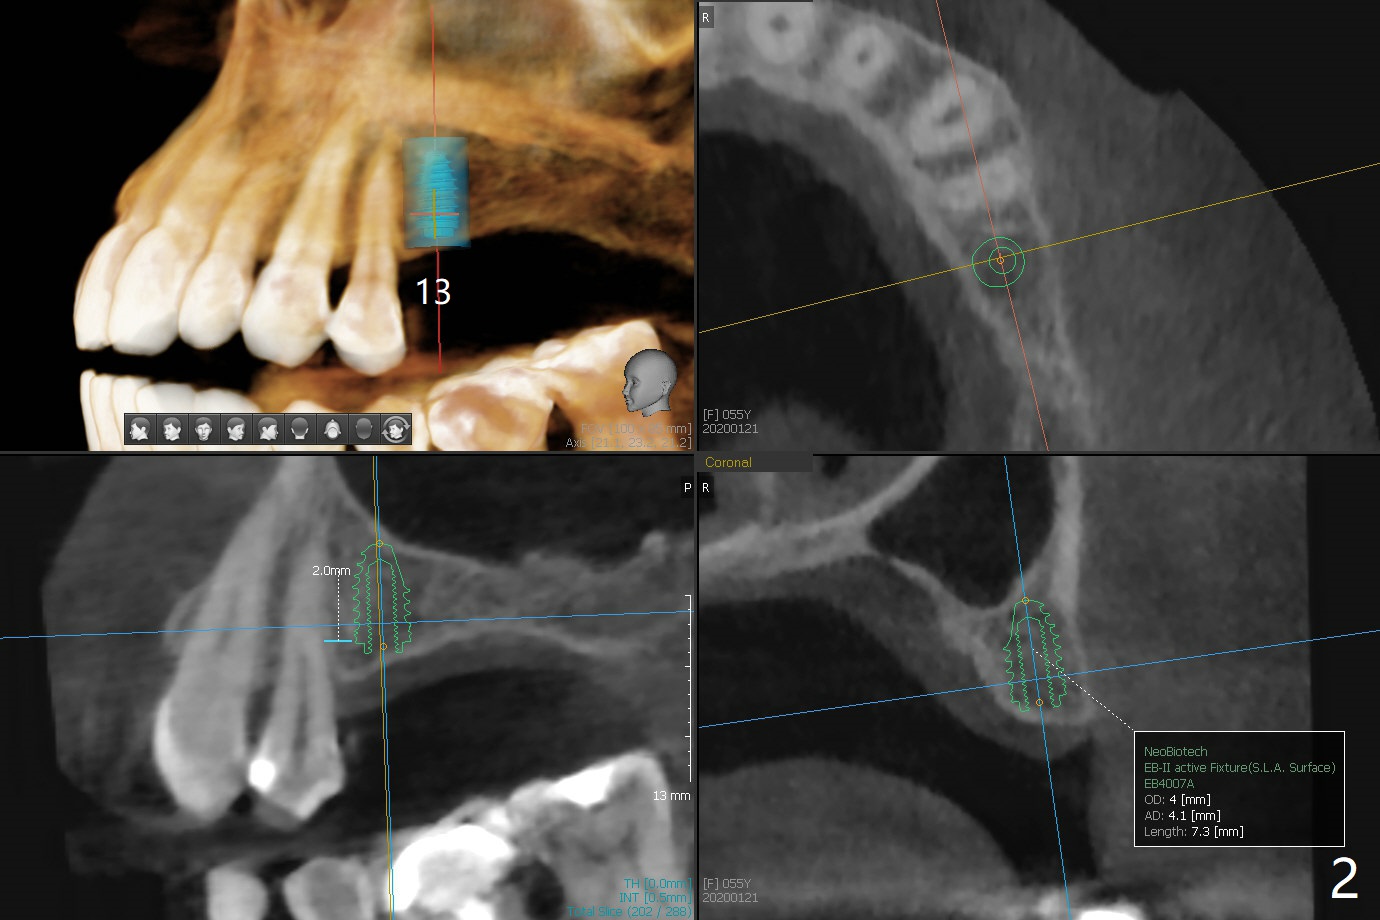

A 55-year-old woman agrees to have implants at #13 and 14 (Fig.1). There is no vertical space for implant at #15 because of supraeruption of #18 (^). A short FC implant will be placed at #13 without sinus lift (Fig.2), while sinus lift is required at #14 (Fig.3) using sinus lift drill or Magic sinus lifter. Prepare PRFx2 and small amount of sticky bone to cover #14 implant. Use acrylic to cover the bone graft. The acrylic will be retained by #13 abutment.